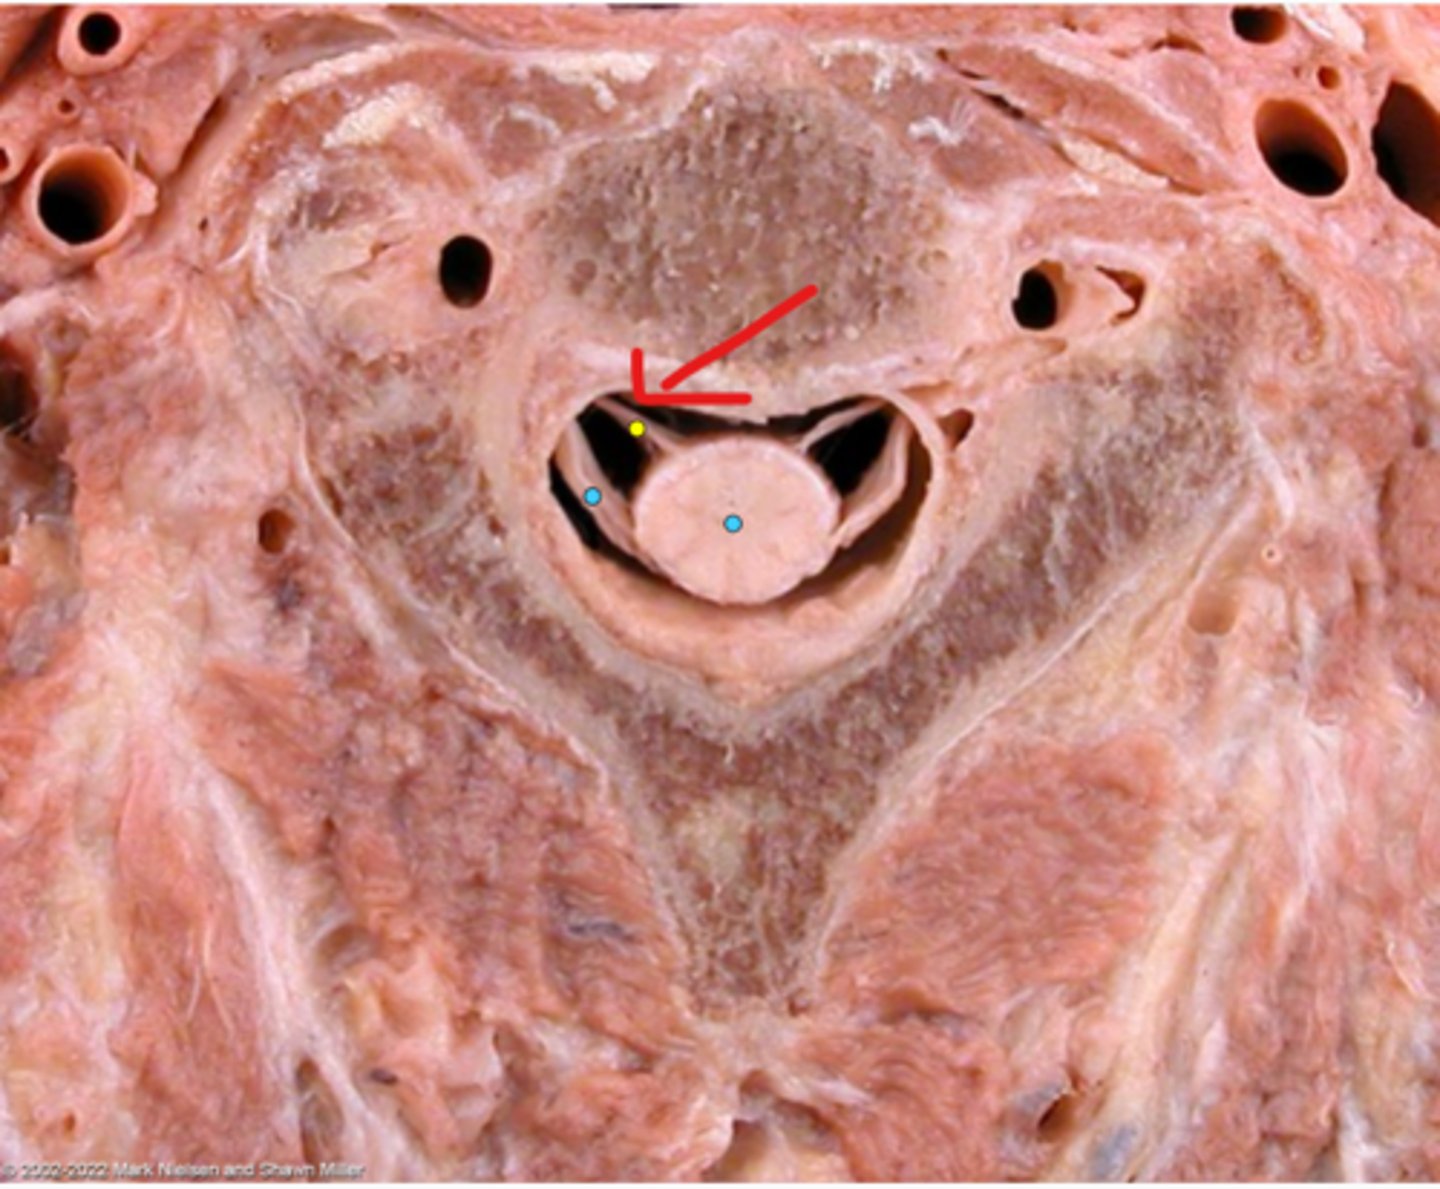

Vertebral foramen

Anterior (ventral) root

Posterior (dorsal) root

Anterior (ventral) rootlets

Posterior (dorsal) rootlets

White matter

Gray matter

Posterior (dorsal) rootlets

Anterior (ventral) rootlets

Spinal cord